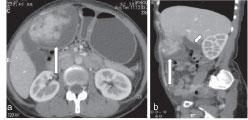

Primary malignant peripheral nerve sheath tumour (MPNST) is an uncommon malignant tumour that arises from the peripheral nerves. Most of these tumours arise in the regions of the trunk, head and neck, or extremities and are rarely seen in the abdomen. In this report, we describe a case of MPNST of the greater omentum, which, to the best of our knowledge, is only the second case reported in the literature. MPNST is an uncommon tumour that can show local invasion and has a high risk of recurrence. We also discuss the utility of "omental vascular pedicle sign" to help establish the omental origin of intra-abdominal masses.

原发性恶性外周神经鞘瘤(MPNST)是一种罕见的起源于外周神经的恶性肿瘤。这些肿瘤大多发生于躯干、头颈部或四肢,很少见于腹部。在本报告中,我们描述了一例大网膜MPNST,据我们所知,这是文献中报道的第二例。MPNST是一种罕见的肿瘤,可表现为局部浸润且复发风险高。我们还讨论了“网膜血管蒂征”在帮助确定腹腔内肿块网膜起源方面的作用。